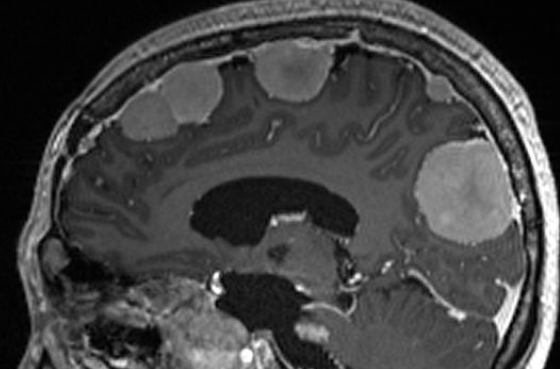

Meningiome Typique (Grade I)

- Bénin

- Masse extra-axiale Parasagittale ++

- Dural Tail

- Forte prise de contraste